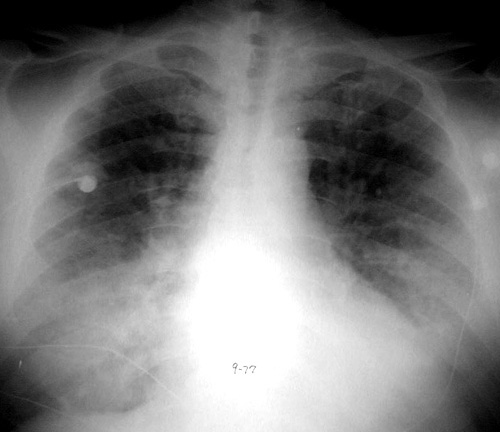

Acute onset bilateral airspace disease due to hemorrhage in a patient with Wegners granulomatosis.